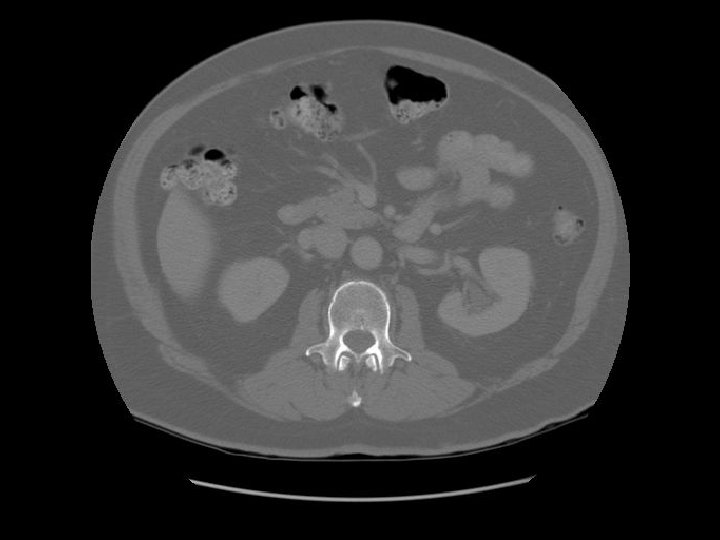

Pancreas Splenic vein The splenic vein lies in the posterior pancreatic grove and joins the superior mesenteric vein to form the portal vein.

Pancreas Duodenal bulb IVC Rt renal artery The right renal artery is retrocaval.

Small cyst in the left kidney.